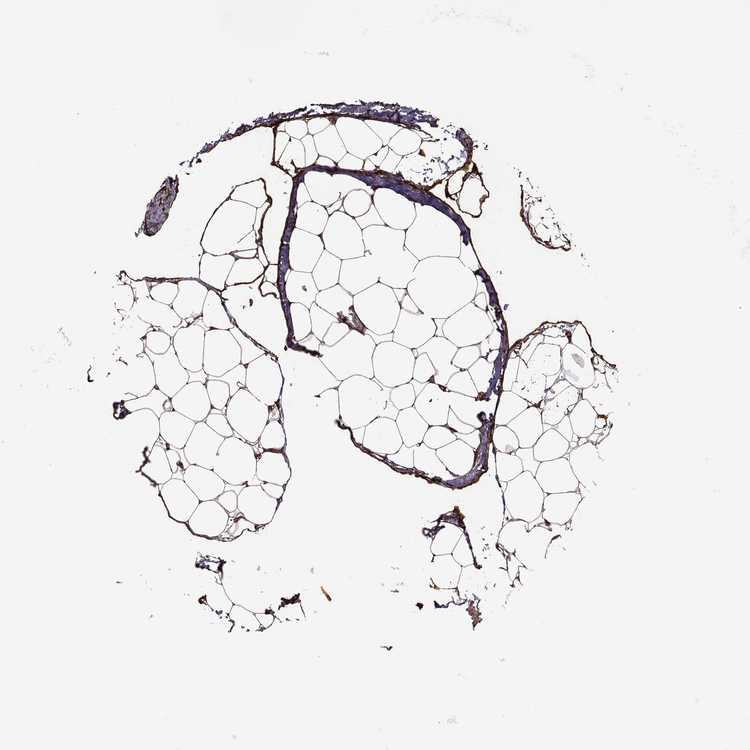

TISSUE PRIMARY DATA SOFT TISSUE Show tissue menu

SOFT TISSUE - Expression summary

SOFT TISSUE 1 - Antibody stainingi

Antibody staining in the annotated cell types in the current human tissue is reported as not detected, low, medium, or high, based on conventional immunohistochemistry profiling in selected tissues. This score is based on the combination of the staining intensity and fraction of stained cells.

Each image is clickable and will lead to virtual microscopy that enables deeper exploration of all samples and also displays staining intensity scores, fraction scores and subcellular localization as well as patient and tissue information for each sample.

Antibody HPA003340Antibody CAB025484

Fibroblasts HighMedium

Peripheral nerve -High

SOFT TISSUE 2 - Antibody stainingi

Fibroblasts MediumMedium

Peripheral nerve HighMedium